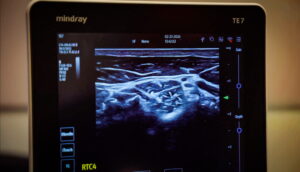

Clinical intervention utilizing Dual Sympathetic Reset (DSR) and Stellate Ganglion Block (SGB) to rapidly reduce physiological stress responses, hypervigilance, and anxiety.